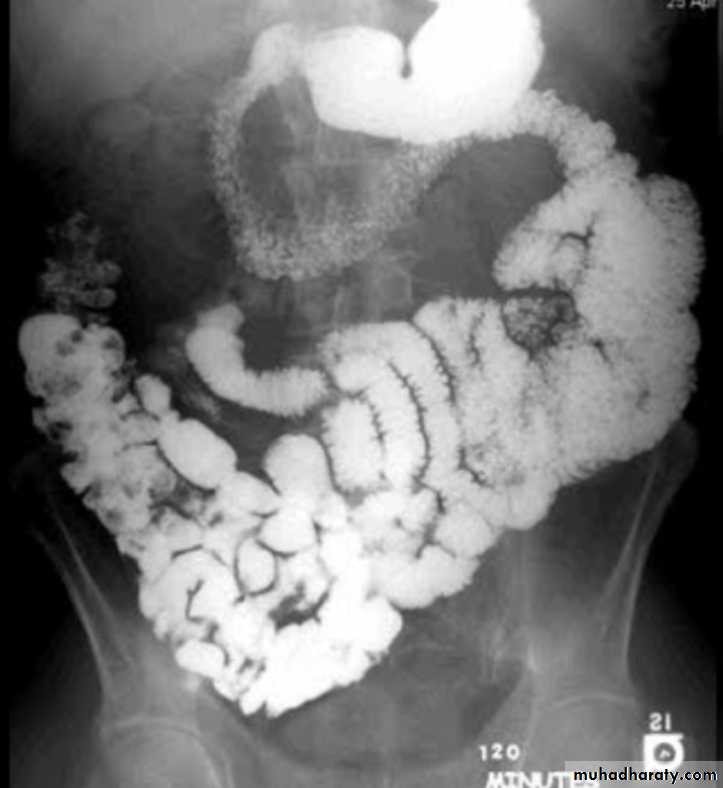

Lymphoma of small bowel

Splaying & separation of the bowel loops due to enlarged LNThickening of the mucosa , irregular in outline ( saw tooth pattern ) .

LATER stage could be present as sign of Mal absorption syndrome ( flocculation & segmentation of the Ba ) .